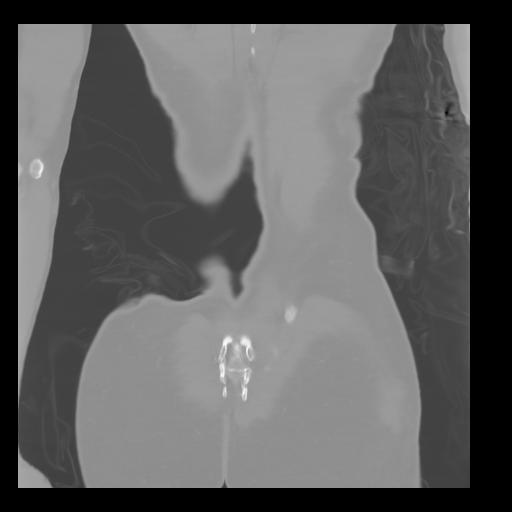

35 CUERPO,CE,Coronal,3.000,CUERPO,Coronal,